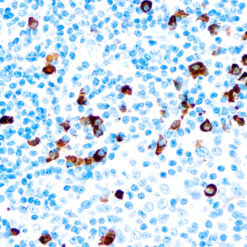

Prostate Specific Antigen, PSA

This product is intended for qualitative immunohistochemistry with normal and neoplastic formalin-fixed, paraffin-embedded tissue sections, to be viewed by light microscopy. Clinical interpretation of staining results should be accompanied by histological studies with proper controls. Patients’ clinical histories and other relevant diagnostic tests should be utilized by a qualified person(s) when evaluating and interpreting results.

| Positive Control Tissue | Prostate carcinoma |